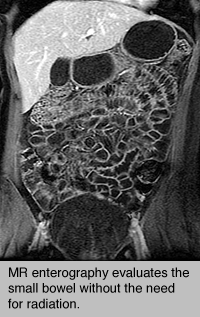

MR enterography evaluates small bowel without the need for radiation.An MR enterography procedure uses magnetic resonance imaging (MRI) technology to obtain detailed images of the small bowel.  MR enterography, also called Magnetic resonance enterography (MRE), is a complementary advanced, accurate and noninvasive diagnostic imaging test to evaluate a broad range of disorders including Crohn's Disease.

The procedure is painless, and there are no known risks, provided the patient has no metal in or on their body and is not pregnant.

In addition to regular preparation for an MRI exam, prior to MR enterography the patient is given two bottles of a special liquid to drink (one bottle 20 minutes before the exam and one bottle 10 minutes before the exam).  The liquid serves to distend the bowel and marks the bowel for clear identification during the imaging study.  Towards the end of the exam the patient is given a small dose of glucagon followed by an injection of gadolinium (an MRI contrast agent).  Glucagon prevents the bowel from moving for a short time, which improves the quality of the images.